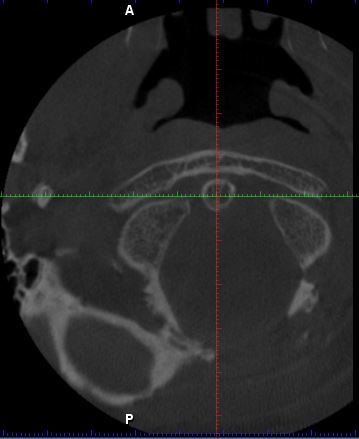

Der HNO Arzt vermutet die Halswirbelsäule als Ursache für den Tinnitus und hat eine DVT anfertigen lassen. Leider kann er die Aufnahmen nicht auswerten und sein Radiologe hat Urlaub. Kann von Euch jemand auf den angehängten Fotos etwas erkennen?

Mann soll die Bilder in 3D anschauen, es ist die ganze datei in dicom format nötig. Einzelne bilder zu schauen ist nutzlos.